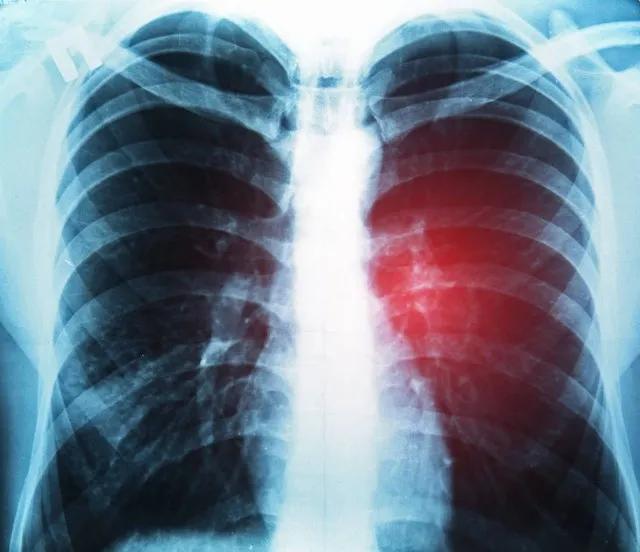

肺结节已成为一种常见的健康问题。据统计,20%左右的人群在体检中会发现肺部结节,但其中绝大多数都是良性的。面对这一情况,我们不必过度恐慌,但也不能掉以轻心。呼吸科医生建议,通过以下三个方法可以有效预防肺结节的发生和发展。

需要强调的是,即使发现肺结节,也不必过分担心。根据大小、密度不同,肺结节的处理方式也有所不同。对于直径小于5mm的微小结节,如果没有高危因素,可以不随访;对于5-10mm的肺小结节,医生会根据具体情况决定复查间隔;只有大于10mm的肺结节,才建议直接手术切除。